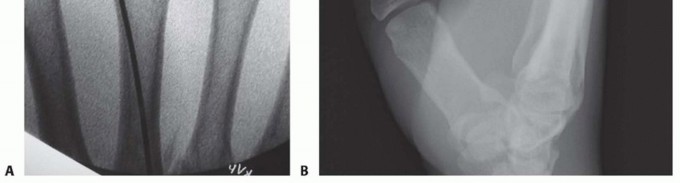

Once reduced, fixation can be achieved via crossed Kirschner wires or retrograde intramedullary pinning (the "bouquet" technique). However, the modern gold standard for minimally invasive fixation is the retrograde intramedullary headless compression screw. A small stab incision is made over the dorsal aspect of the flexed MCP joint. The entry portal is meticulously established in the articular "safe zone" of the metacarpal head—specifically the dorsal-ulnar or dorsal-radial collateral recess, strictly avoiding the central weight-bearing articular cartilage.

A guidewire is advanced down the medullary canal across the fracture site under fluoroscopic guidance. After confirming perfect rotational alignment and length, the canal is sequentially broached or drilled, and an appropriately sized headless compression screw is buried beneath the articular cartilage. This technique provides robust, load-sharing stability that allows for immediate, unrestricted active range of motion, vastly reducing the incidence of postoperative stiffness compared to traditional K-wire constructs.

Clinical & Radiographic Imaging Archive